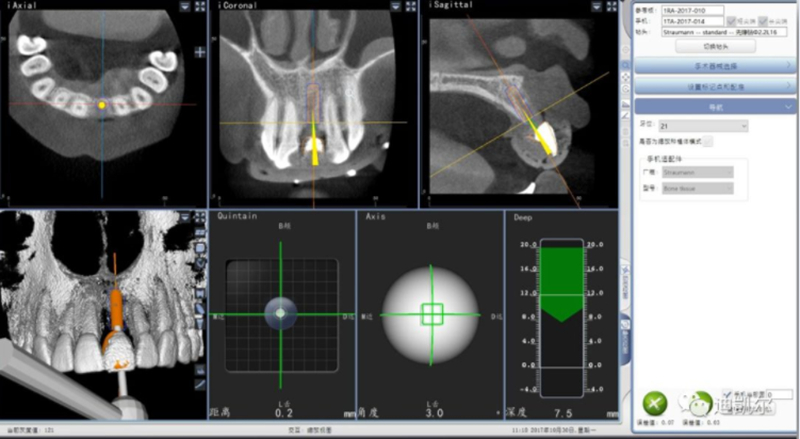

設(shè)計軟件中,選擇適合的種植體

根據(jù)修復(fù)體形態(tài),軸向以及骨量將種植體放置最適合的位置